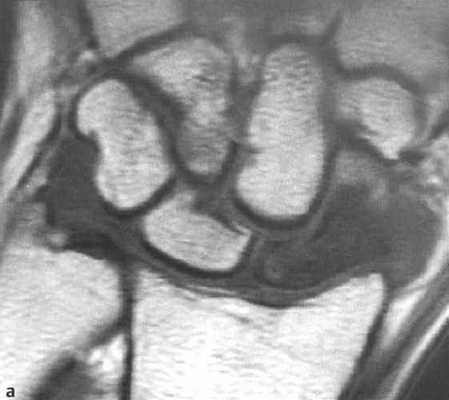

а-d Перелом ладьевидной кости. МРТ. (а) Неконтрастное Т1-взвешенное изображение демонстрирует распространенные участки снижения интенсивности сигнала.

(b) Последовательность SТ1R демонстрирует гиперинтенсивный сигнал с гипоинтенсивной линией перелома.

(с) Т1 -взвешенное изображение после введения контрастного вещества. Проксимальная часть ладьевидной кости не накапливает контрастное вещество, что означает нарушение кровоснабжения и лишение жизнеспособности.

(d) Длительно существующий некроз ладьевидной кости с резорбцией проксимального фрагмента, дегенеративными изменениями, поражающими лучезапястный сустав с нестабильностью запястья и уменьшением высоты запястья.